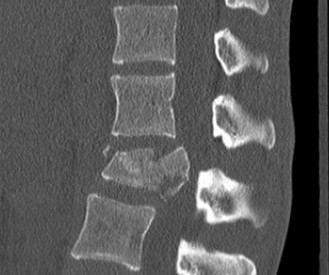

The correct answer is (A). As the case scenario strongly suggests an injury to the spine at the thoracolumbar junction, a CT scan of both the thoracic and lumbar regions is indicated. An MRI should not be the first imaging study obtained. Standing films should not be obtained in a trauma patient with a potentially unstable spine injury. A CT myelogram would only be obtained if an MRI was indicated but the patient had a contraindication to an MRI. Images of the above patient are shown inFigures 1–25 and 1–26. This injury is best characterized as which of the following? 1. Compression fracture

Figure 1–25

Figure 1–26

The correct answer is (B). The images demonstrate an L1 vertebral body fracture with a small degree of kyphosis. There is comminution of the vertebral body with a posterior vertebral body fragment that is slightly retropulsed into the spinal canal. This separate posterior vertebral body fragment (which is noncontiguous with the pedicles) is the hallmark of a burst fracture. Compression fractures do not have any posterior vertebral body involvement. A Chance fracture, also known as a seat belt fracture or flexion–distraction injury, will exhibit distraction of the posterior elements through bone, bone-ligament, or purely ligament structures, with an axis of rotation somewhere within the anterior vertebral body or anterior to the vertebral body. A fracture dislocation exhibits translational deformities between the injured levels. While there appears to be a translational deformity on the sagittal CT, the vertebral bodies of the uninjured levels above and below are actually well aligned.

An MRI was obtained of this patient. Your review as well as the radiologist’s

review clearly demonstrate that there is no posterior ligamentous disruption. The next step in management should be:

The correct answer is (D). Considering that the posterior ligamentous complex is not disrupted, which is generally held to be the key to fracture stability, this injury would be best characterized as a stable thoracolumbar burst fracture. Randomized controlled trials have demonstrated that operative and nonoperative treatment of this injury results in equivalent clinical results. Surgical treatment, as described in choices A, B, or C, would be options if the patient had an unstable fracture, that is, posterior ligamentous complex disruption or a neurological injury that would benefit from decompression. With equivalent clinical outcomes and the avoidance of operative complications, nonoperative treatment would be best. The patient may benefit from a thoracolumbosacral orthosis (TLSO); mostly by comfort. It is usually prudent to get a set of upright radiographs (in the brace) to confirm stability of the fracture prior to discharge. Objectives: Did you learn...? To evaluate patients with suspected thoracolumbar spinal trauma?